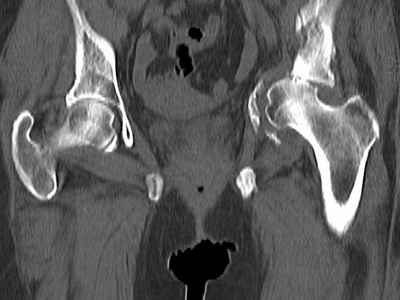

Уважаемые коллеги, возник вопрос по лечению нашей пациентки 60 лет. Около года назад множественная травма: в том числе Т-образный перелом вертлужной впадины. На сегодняшний день сращение отломков имеется на ограниченных участках, имеется дефект задней колонны вертлужной впадины. Движения неплохие, ходит с костылями, приступая на ногу. По мнению эдопротезистов при установке антипротрузионного кольца или октопуса не хватит костного материала и необходимо перед протезированием выполнить реконструкцию впадины, иначе чашка протеза неминуемо выпадет.Просьбы поделиться положительным и отрицательным опытом протезирования в подобных случаях.Возможно ли обойтись без реконструкции?Или лучше с ней?С уважением РАВ.

По моему мнению предварительну реконструкцию делать нет необходимости. Операцию надо выполнять одномоментно с пластикой вертлужной впадины. по поводу того, что не хватит головки. Да не исключено. Но ведь есть и другие материалы. Лучше при таком раскладе иметь в запасе замороженную головку. если нет возможности, как вариант два крыла подвздоной кости + хронос или его аналоги. По поводу выбора конструкции. Октопус в данной ситуации будет совсем не уместен, т.к. имеется дефект задней колонны вертлужной впадины. Да как конструкция октопус встанет не плохо. Но в функциональном плане не будет хорошей задне латерально и заднемедиальной точек опры впадины на период перестройки трансплатов. И по этому в данной ситуации более уместно кольцо Бурх(г)-Шнайдера с аналогичной пластикой, но возможнотью зафиксировать отломки задней колонны, крыши. Естественно цементная чашка с козырьком из кросс линк полиэтилена. Гололвка керамика, ножка бесцементная можно Цваймюллера или любой другой конструкции, они сейчас все хороши.

Основное внимание необходимо уделить стабильности костных фрагментов в зоне перелома вертлужной впадины. Если имеется нестабильность я предпочел бы Октопус для остеосинтеза и стабильности вертлужной впадины. Этот момент является основным для успешного протезирования.

Если впадина единое гнездо по окружности, достаточно антипротрузионного кольца или Буршнайдера.